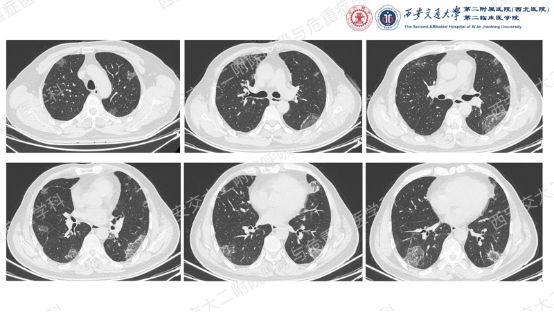

让我们一起从影像入手,看看这名患者的胸部CT特征:双肺多发斑片、实变和磨玻璃影,胸膜下和支气管血管束周围分布为主,病灶无明显空洞、钙化,可见散在支气管充气征,反晕征(中心磨玻璃影 + 外周环形实变影)尤为显著,伴典型“环礁征”(病灶边缘呈结节状隆起,类似环礁形态)。基于这些特征性影像学表现,同时排除细菌、真菌、结核感染及结缔组织病、肿瘤等常见病因,临床诊断隐源性机化性肺炎(COP)。

一般来说,OP诊断的第一线索来自影像学特征,若患者经规范抗感染治疗后病灶无改善,结合病理改变(典型表现为肺泡内、肺泡管、呼吸性细支气管及终末细支气管腔内息肉样肉芽组织增生,伴少量炎症细胞浸润,肺结构基本保留,无明显纤维化),排除其他疾病后即可确诊。病理检查是诊断的金标准,但部分患者因活检样本局限(如TBLB取材表浅),可能仅表现为慢性炎症,无法获得典型病理证据。

本例患者虽未获得典型的病理确诊依据,但结合其“双肺多发胸膜下病灶、反晕征+环礁征”的特征性影像学表现、抗感染治疗无效的临床经过,以及全面排除感染、肿瘤、结缔组织病等其他病因,临床诊断COP的依据已充分。